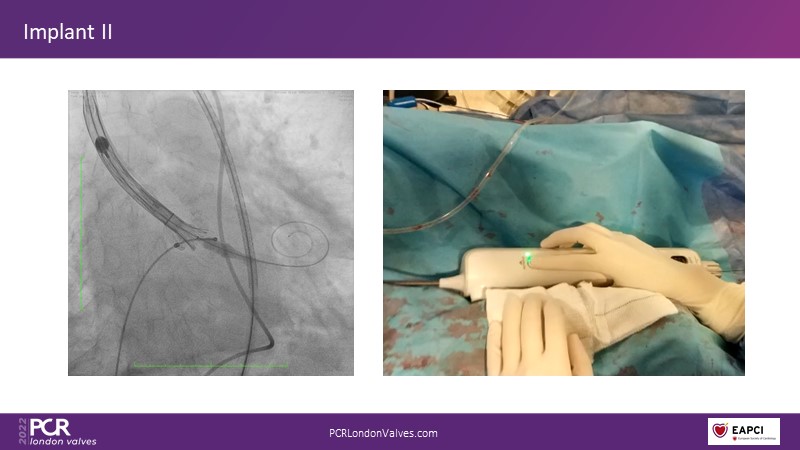

In this session, a panel of experts introduce the VitaFlow TAVI system, a good option for patients with complex anatomies. They also present the five-year results of VitaFlow in severe aortic stenosis.

- To discuss the use of VitaFlow in bicuspid aortic valve stenosis

- To understand the outcomes of VitaFlow Liberty in pure aortic regurgitation